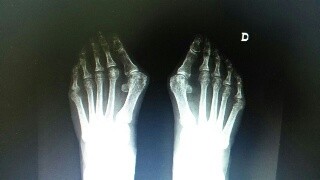

Mucha tinta tendríamos que gastar si quisiéramos escribir todo lo relacionado con los famosos “juanetes”. Vamos a dar aquí unos apuntes sobre los juanetes, como se produce, cuales son sus consecuencias, cuando aparece y su tratamiento.